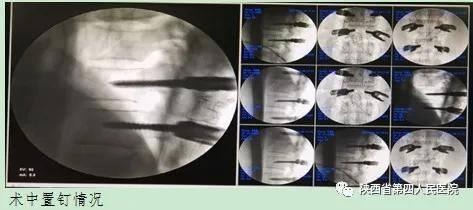

患者入院后 , 骨科三病区专家团队详细询问病史 , 患者腰部疼痛及双下肢麻木无力 , 排尿困难 , 经过详细查体和完善相关检查后 , 诊断明确 , 积极的术前讨论后患者腰1椎体爆裂骨折 , 骨块移位压迫脊髓神经 , 脊髓损伤 , 神经功能受损明确 。 需急诊立即先行腰椎切开复位椎管探查减压内固定术、择期再行右股骨干骨折切开复位髓内钉内固定术 , 同时术前给予右下肢胫骨结节骨牵引术后 , 输血补液同时 , 积极术前准备 。 经医院围手术期管理团队术前充分评估讨论患者各项检查检验结果 , 制订术前手术预案、术中精细化管理方案 , 采取俯卧位麻醉通气策论保障生命体生稳定 , 控制性降压、缩短手术时间等方式减少术中出血 , 在麻醉科的大力配合下顺利完成腰椎切开复位椎管探查减压内固定手术 , 术后麻醉恢复室苏醒 , 检查患者双下肢活动及肌力 , 双下肢麻木无力症状明显缓解顺利安返病房继续精心治疗 , 并安排下一阶段手术方案 。

腰椎切开复位椎管探查减压内固定手术后第9天患者恢复良好 , 再次启动医院围手术期管理团队进行综合评估 , 专家们一致认为患者腰椎切开复位椎管探查减压内固定手术成功、目前各项生命体征平稳 , 可行右股骨干骨折切开复位髓内钉内固定术 。 骨科三病区专家再次给患者实施了右股骨干骨折切开复位髓内钉内固定术 , 术中配血防止短期2次手术造成患者术后急性贫血 , 影响患者术后快速康复 , 目前患者处于恢复期 , 神经功能需进一步的康复治疗 。 手术效果得到了病人和家属的一致肯定和赞赏 , 骨科三病区医护人员用悉心照料、设身处地的为患者及家属着想的工作态度 , 救死扶伤、大爱无疆的崇高精神体现了我院医护人员“爱心、精心、专心、放心”职业精神 , 患者对医务工作的感谢无法用言语表达 。